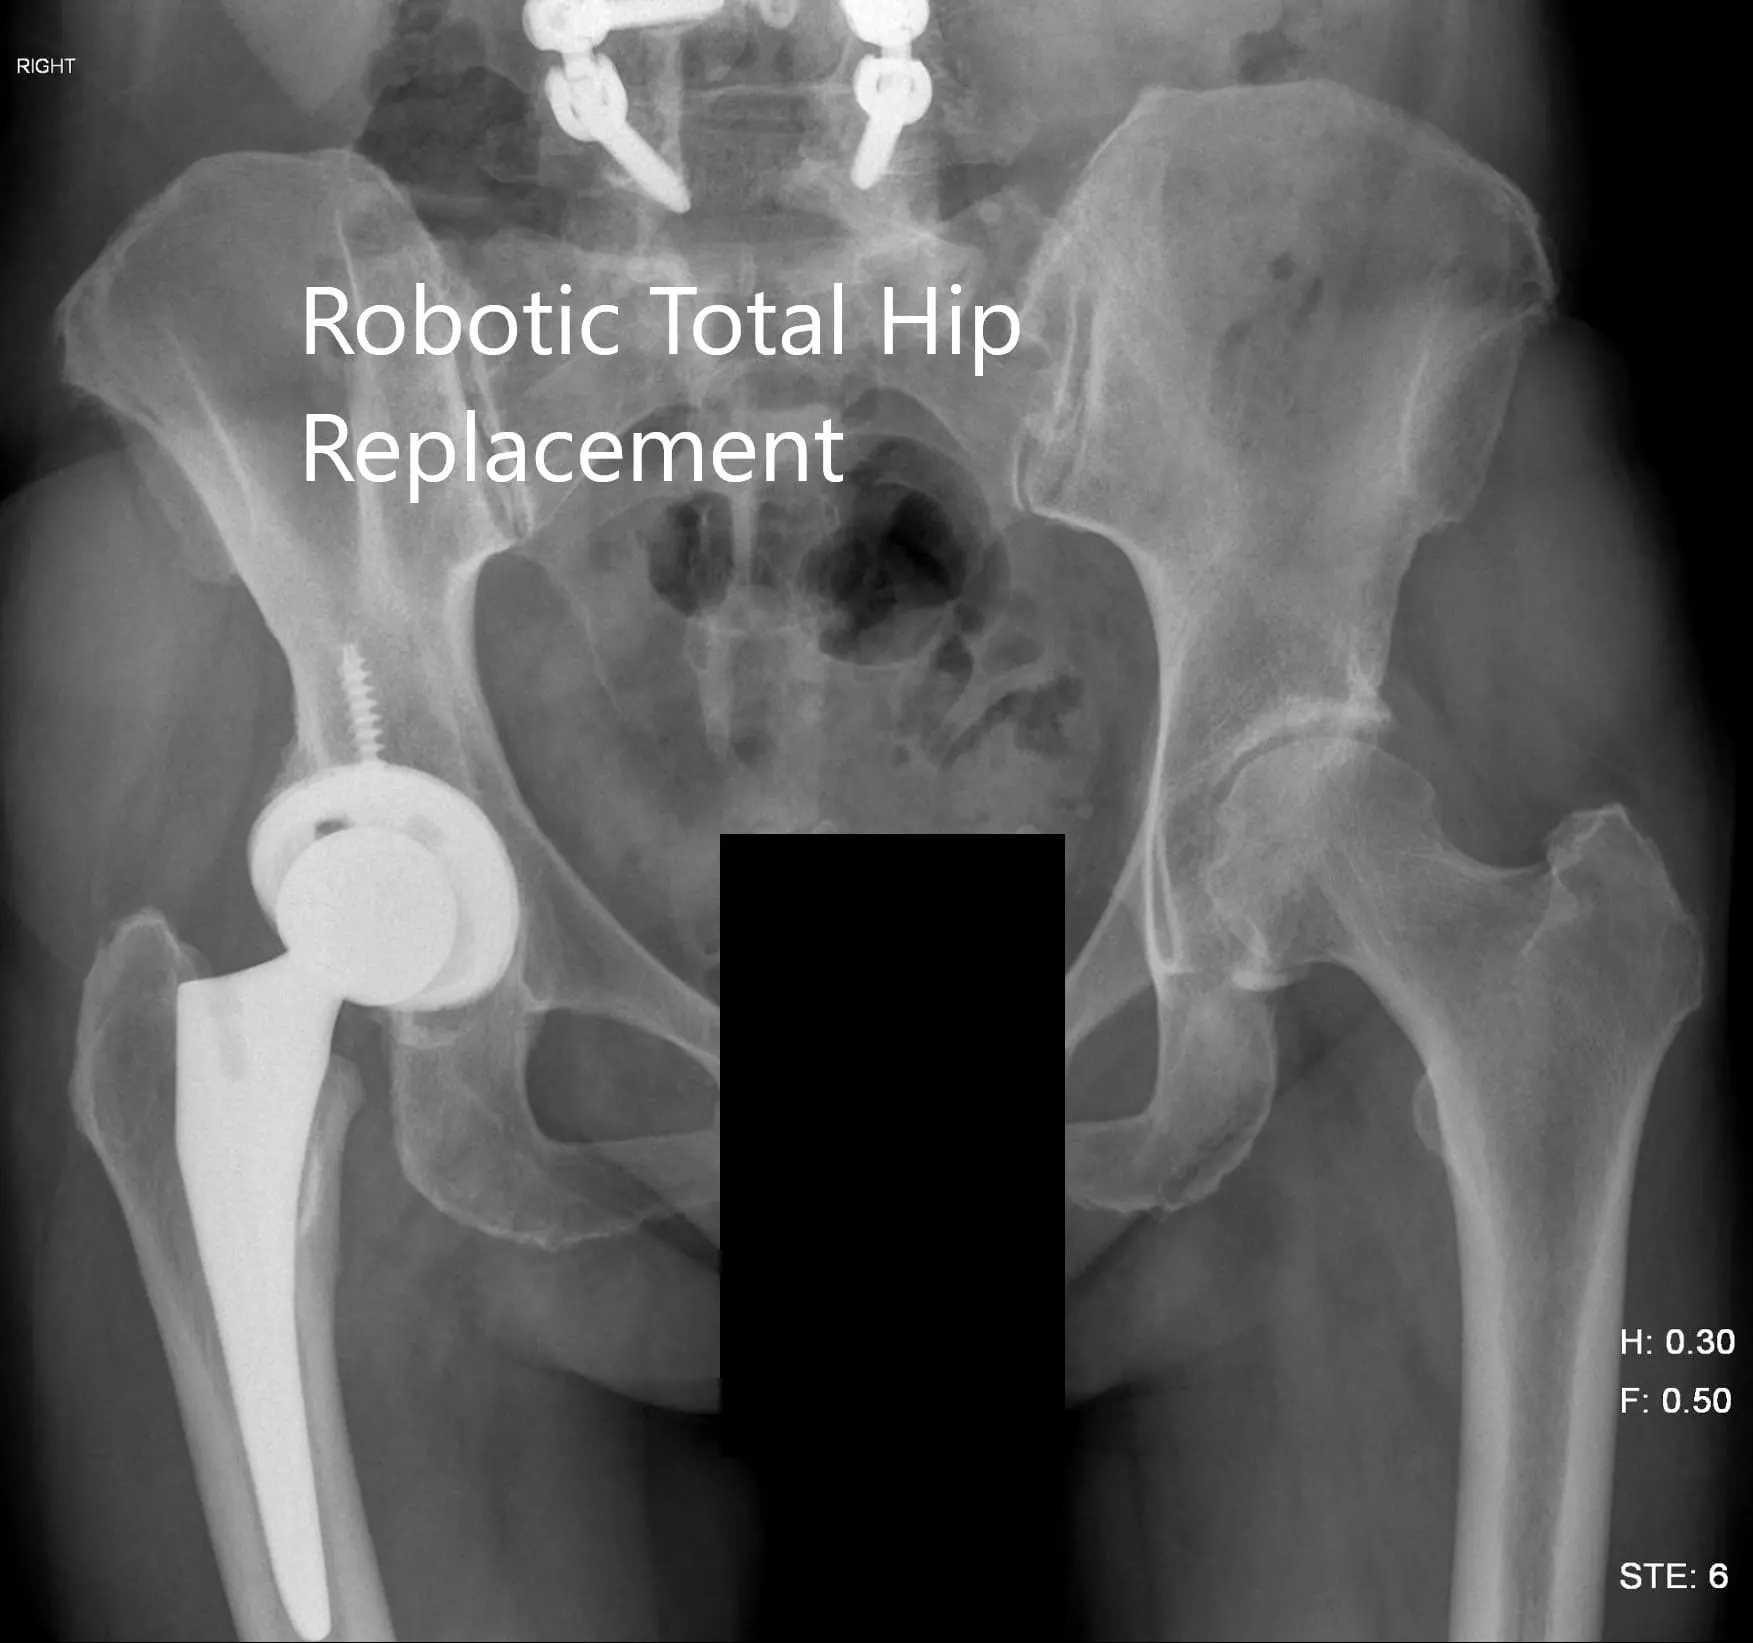

OPERATION: Robotic right total hip replacement.

IMPLANTS USED: Tritanium cluster shell 52-mm with 6.5-mm x 30-mm screw with a Trident shell. Zero degrees poly with a 127-degree stem with a ceramic head, outer diameter 32-mm minus 4.

Postoperative X-ray of the pelvis showing AP view.